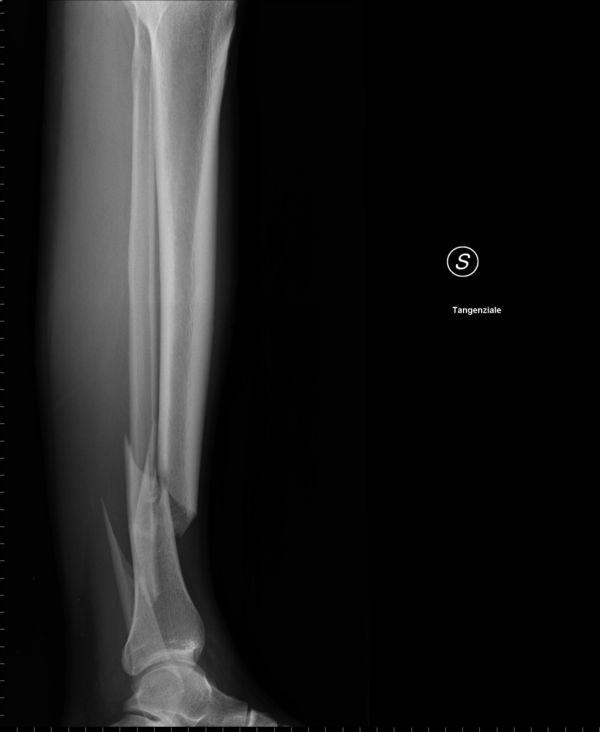

mariusz-w napisał(a):Posiadam także zdjęcia nie rentgenowskie, a wykonane aparatem w telefonie , ale tymi nie będę Was straszył.

longtom napisał(a): A swoją drogą jak skręcam jakieś deseczki albo inne beleczki to wkręty z drugiej strony mi nie wystają.

Ale z kościami widocznie inaczej się robi.